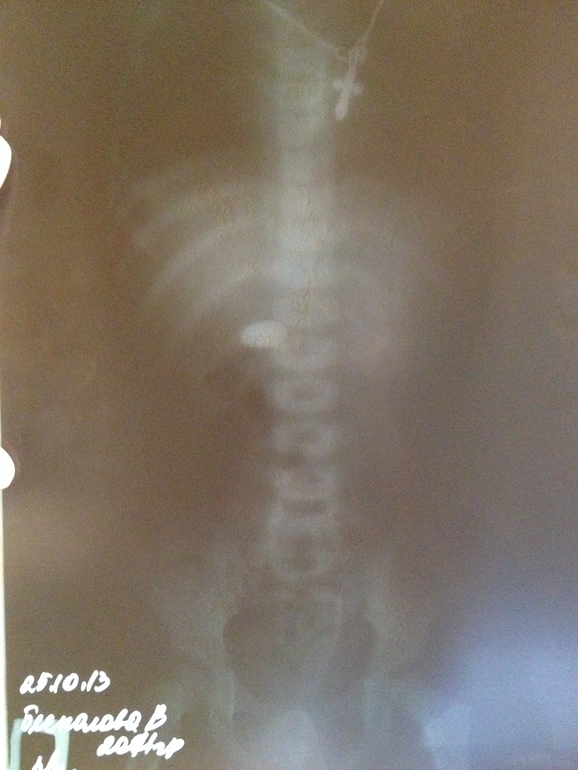

Сегодня утром я ездила с Викторией в больницу, опять сделали ренген. Продвижение есть, по снимку 1,5-2 см. Врач говорит, еще рано судить, вышло это из желудка или нет. Если выйдет, то это супер, естественный и прямой выход это лучшее для нас. Либо это осядет в желудке и это стремно, чур нас, чур! Врач сразу сказал, это не монета! А, что же это??? Предлогает лечь в больницу. Я поинтерисовалась для каких целей. Ребенок довольный радостный, ведь у нее теперь есть свой сюрприз, о котором никто не знает, что это) Сказала, просто будут наблюдать. А когда будет в прямой кишке, сделают клизму. Вот какая веселуха 3 дня в пустую там лежать. А если нет то в воскресение сделают рентген и в понедельник, чур, чур!!! Я договорилась что дома посмотрю и в воскресение приедем на рентген. Врач меня просила не забыть, даже записать где-нибудь. Вот как о таком можно забыть?!!! Я ночь не спала, а она не забудьте)))

Я ехала домой и очень долго рассматривала снимок, крутя его как можно, что же это такое, уже не кружок, а овальчик!!! хм...где-то я это видела...